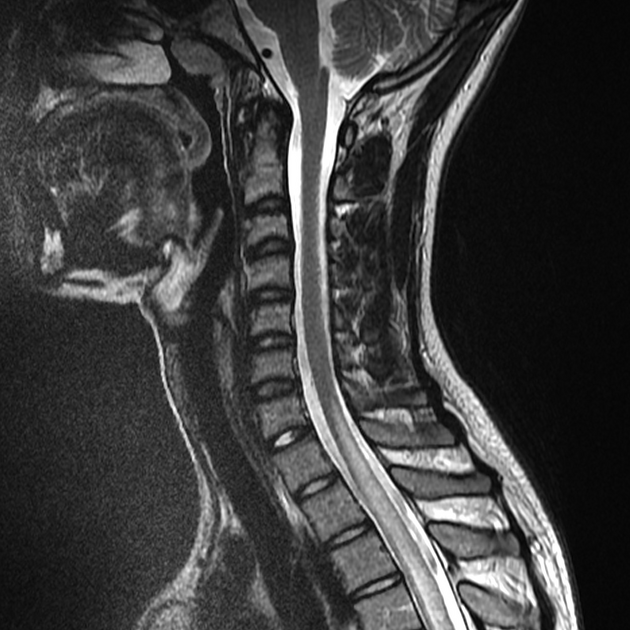

É fundamental trazer todos os exames realizados anteriormente (imagens de ressonância em CD/Link e laudos, exames de sangue e líquor). Também recomendamos anotar todas as suas dúvidas e os medicamentos que está utilizando no momento.

NMO

Cuidado específico para espectro NMOSD, focado na prevenção de surtos e controle inflamatório.